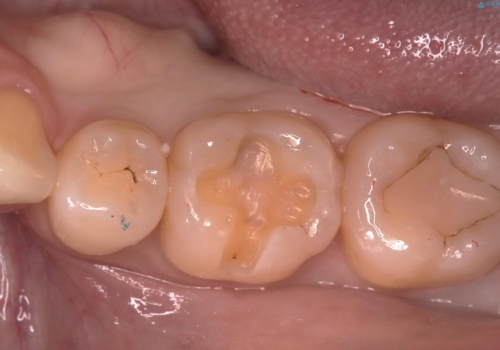

- 主訴:笑った時に下の歯のポラスチックが茶色くなっているのが気になる

過去に虫歯の治療を受けた歯の噛む面に充填されているプラスチック材料が劣化し、歯質とプラスチック材料との境目に生じたギャップに汚れが溜まっている状態だったため、物性の安定したセラミックインレーにてやり替えとなりました。

充填されているプラスチックの材料を除去したところ、う蝕が広がっていたため除去しCR裏層の後セラミックインレー修復をしています。セラミックインレーセット時は、ラバーダム防湿を行っています。